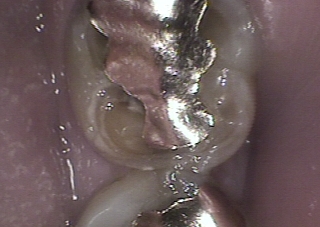

例えばこの歯、

レントゲンを撮ってみると、

このように写ります。

このレントゲンから、この歯は神経を取っている歯であると分かるものの、一箇所

“ 覗けてないところ ”

があります。

それは金属の中です。

金属はレントゲンを通さない為、真っ白に写ります。

この金属に隠れた部分で何が起こっているのかどうしても知りたいときがあります。

金属を外せばすぐに分かることなのですが、できれば外す前に正確な情報が欲しいというのが本音です。